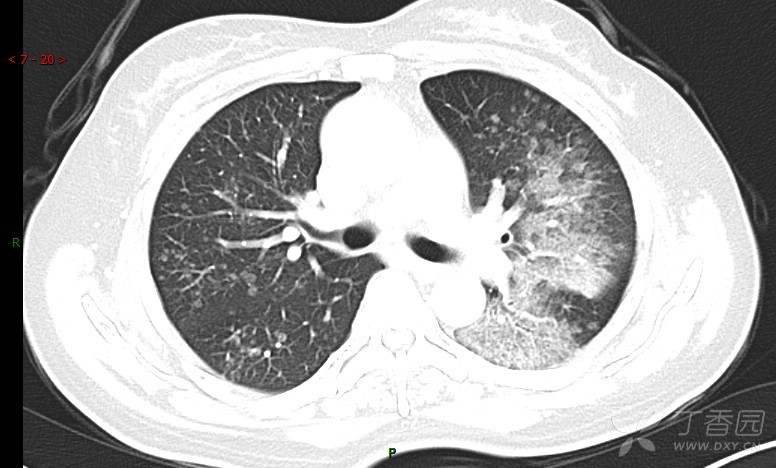

腺泡结节影,蜂窝征,这些都在提示……(病例3连发,附其他2例链接,病理已公布)

咳嗽1年余,加重7天。

患者于1年余前始受凉后出现咳嗽,多为干咳,未在意,未到医院就诊。近3月患者出现咳痰,多为黄色粘痰,量大,伴乏力,偶有头晕、心慌,无发热、胸痛、憋喘,无低热、盗汗、咯血、胸痛,无头痛,无恶心、呕吐、腹痛、腹泻,无尿频、尿急、尿痛,在当地诊所给予抗感染等对症支持治疗(具体药物及剂量不详),症状仍时有反复。患者于1月余前到外院就诊,行胸部CT提示双肺炎症,左肺重,考虑为“间质性肺炎”,给予“左氧氟沙星、利巴韦林、头孢哌酮舒巴坦钠注射液”治疗,复查胸部CT示病灶吸收不理想,后出院继续于诊所对症治疗(具体药物及剂量不详),效果欠佳。7天前患者无明显诱因出现上述症状加重,为求进一步诊治,特来我院就诊,我院门诊以“肺炎(重症)?”收入留观室,留观室给予“盐酸莫西沙星氯化钠”等对症治疗后,今日转入我科。患者自发病以来,神志清,精神差,饮食正常,睡眠增多,大小便正常,体重近3月减轻5公斤余。